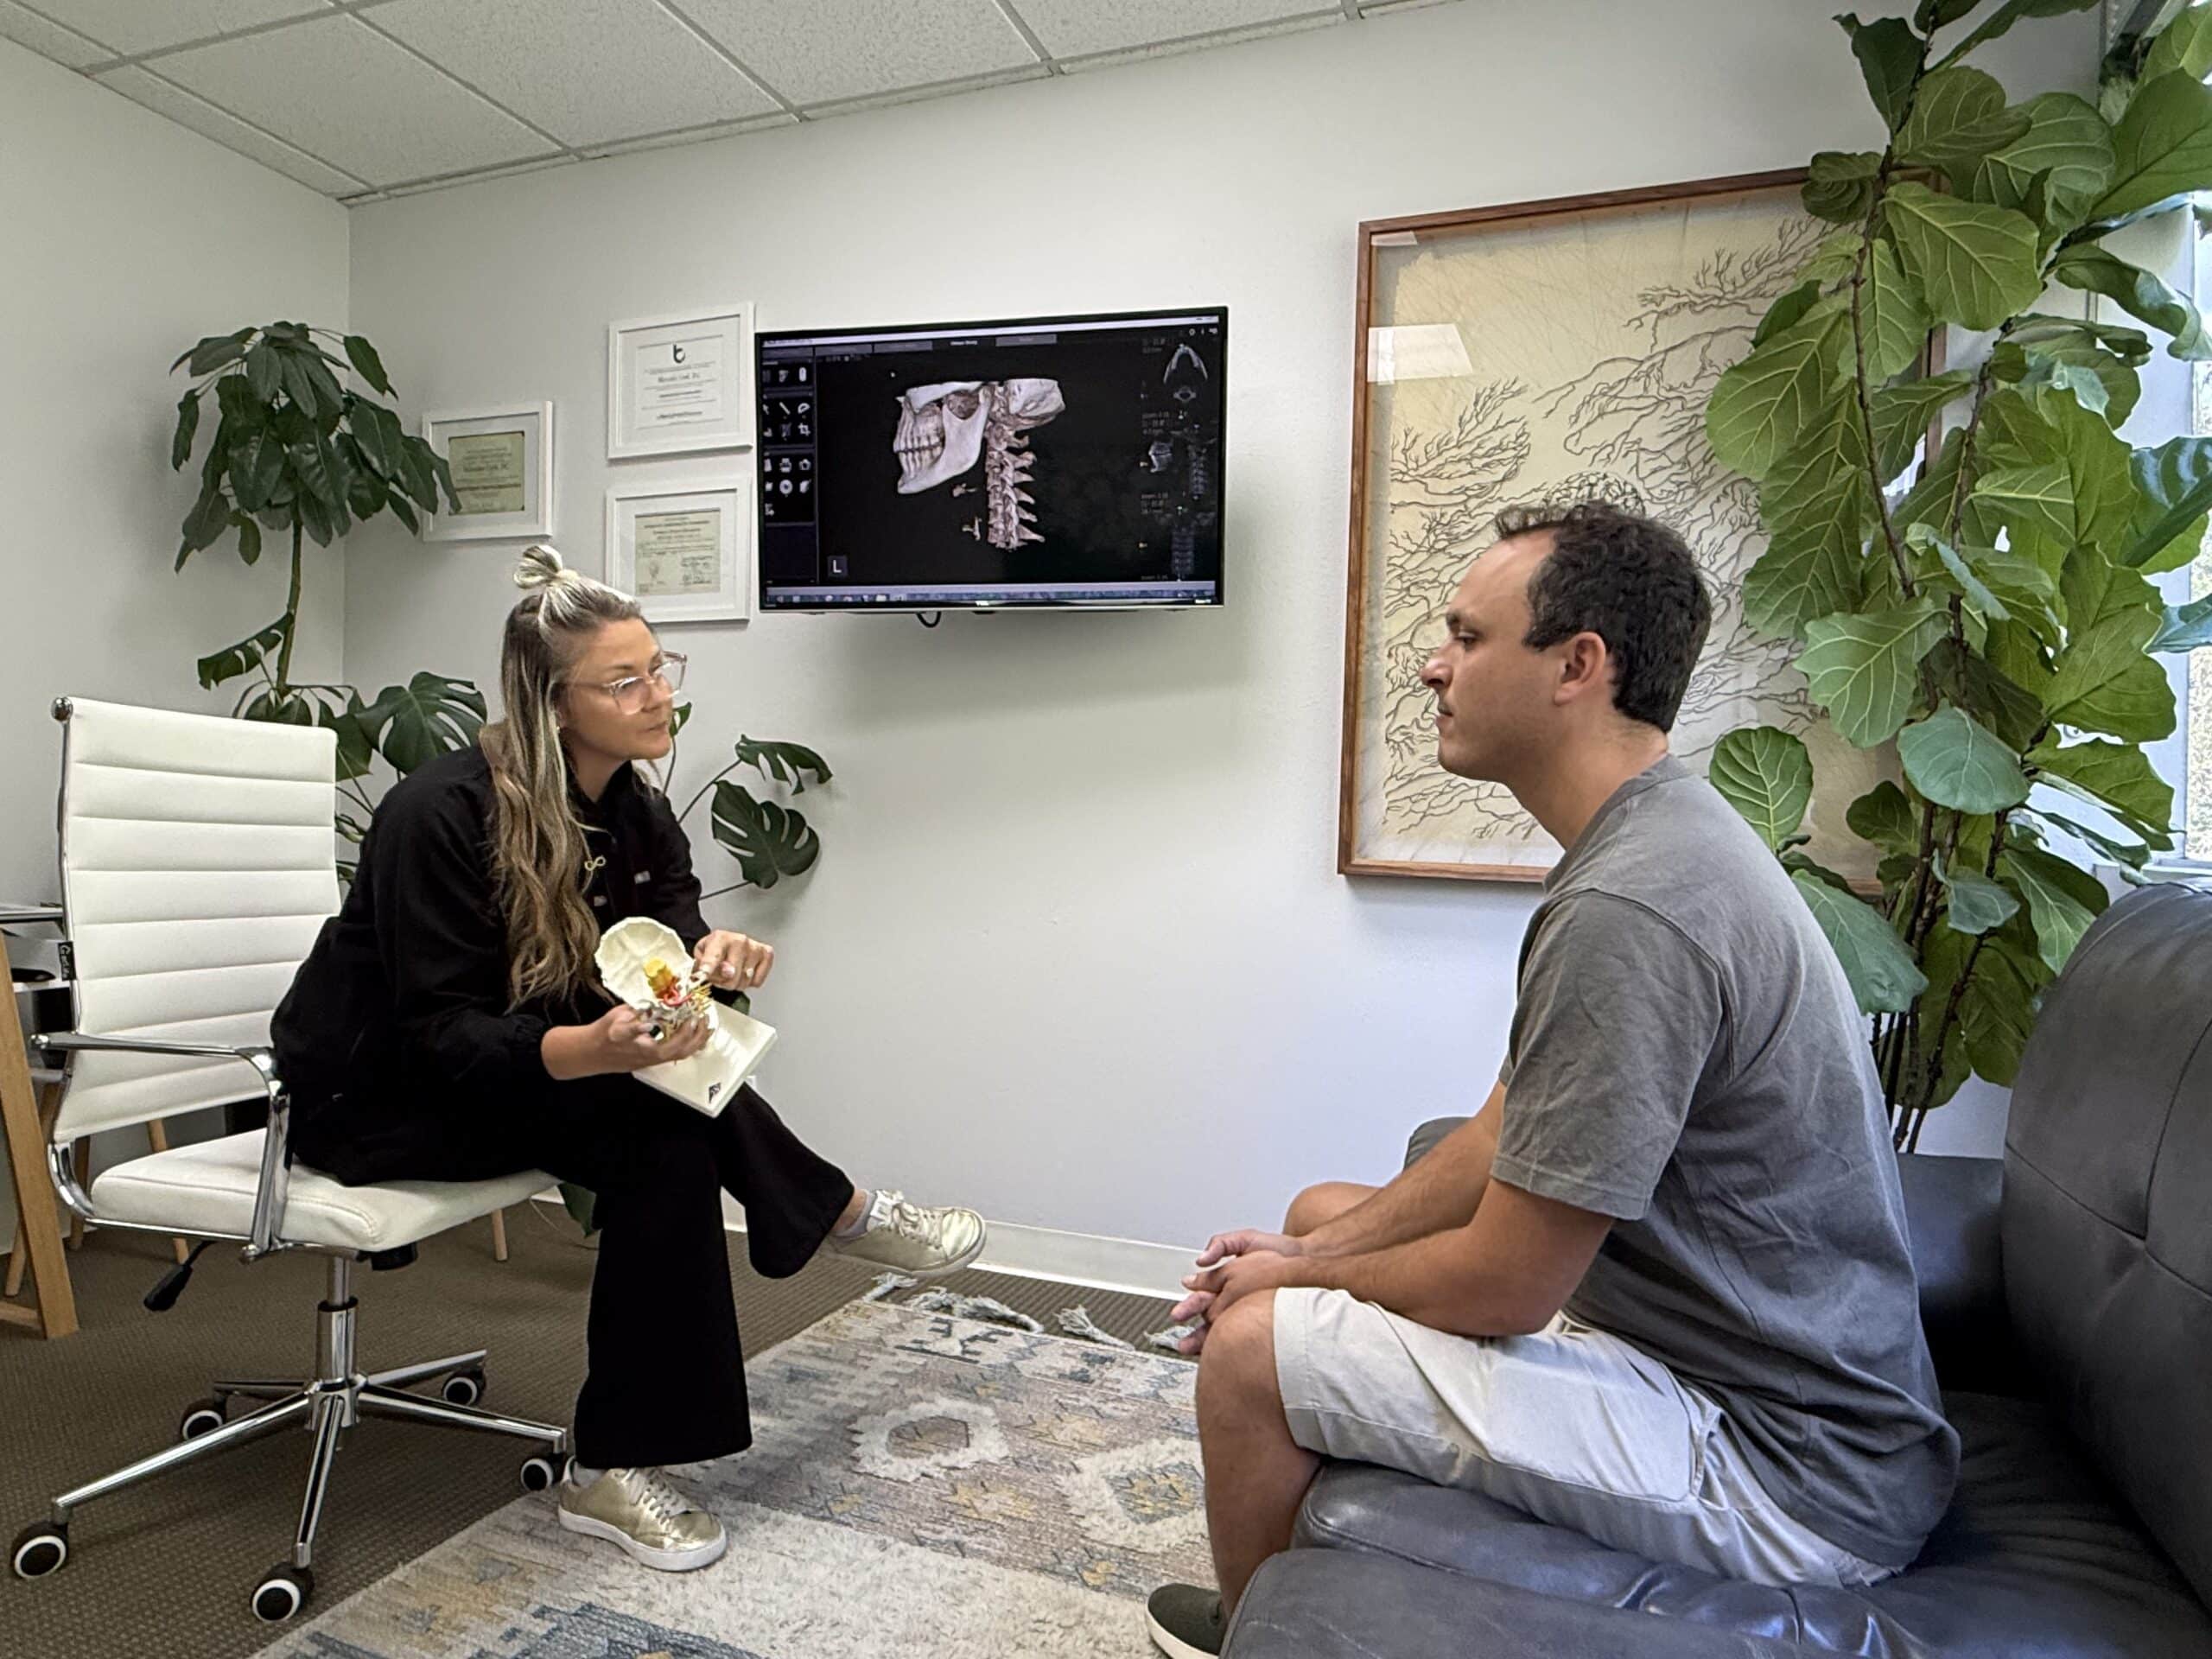

Upper Cervical chiropractors use highly specialized X-rays and adjustments that are specifically tailored to your anatomy. No two people are the same, every individual is unique and therefore has different needs.

Such specialized X-rays allow the doctor to pinpoint which vertebrae are out of alignment and where in space it has moved. No other traditional chiropractor uses this system of analysis except for Upper Cervical doctors.